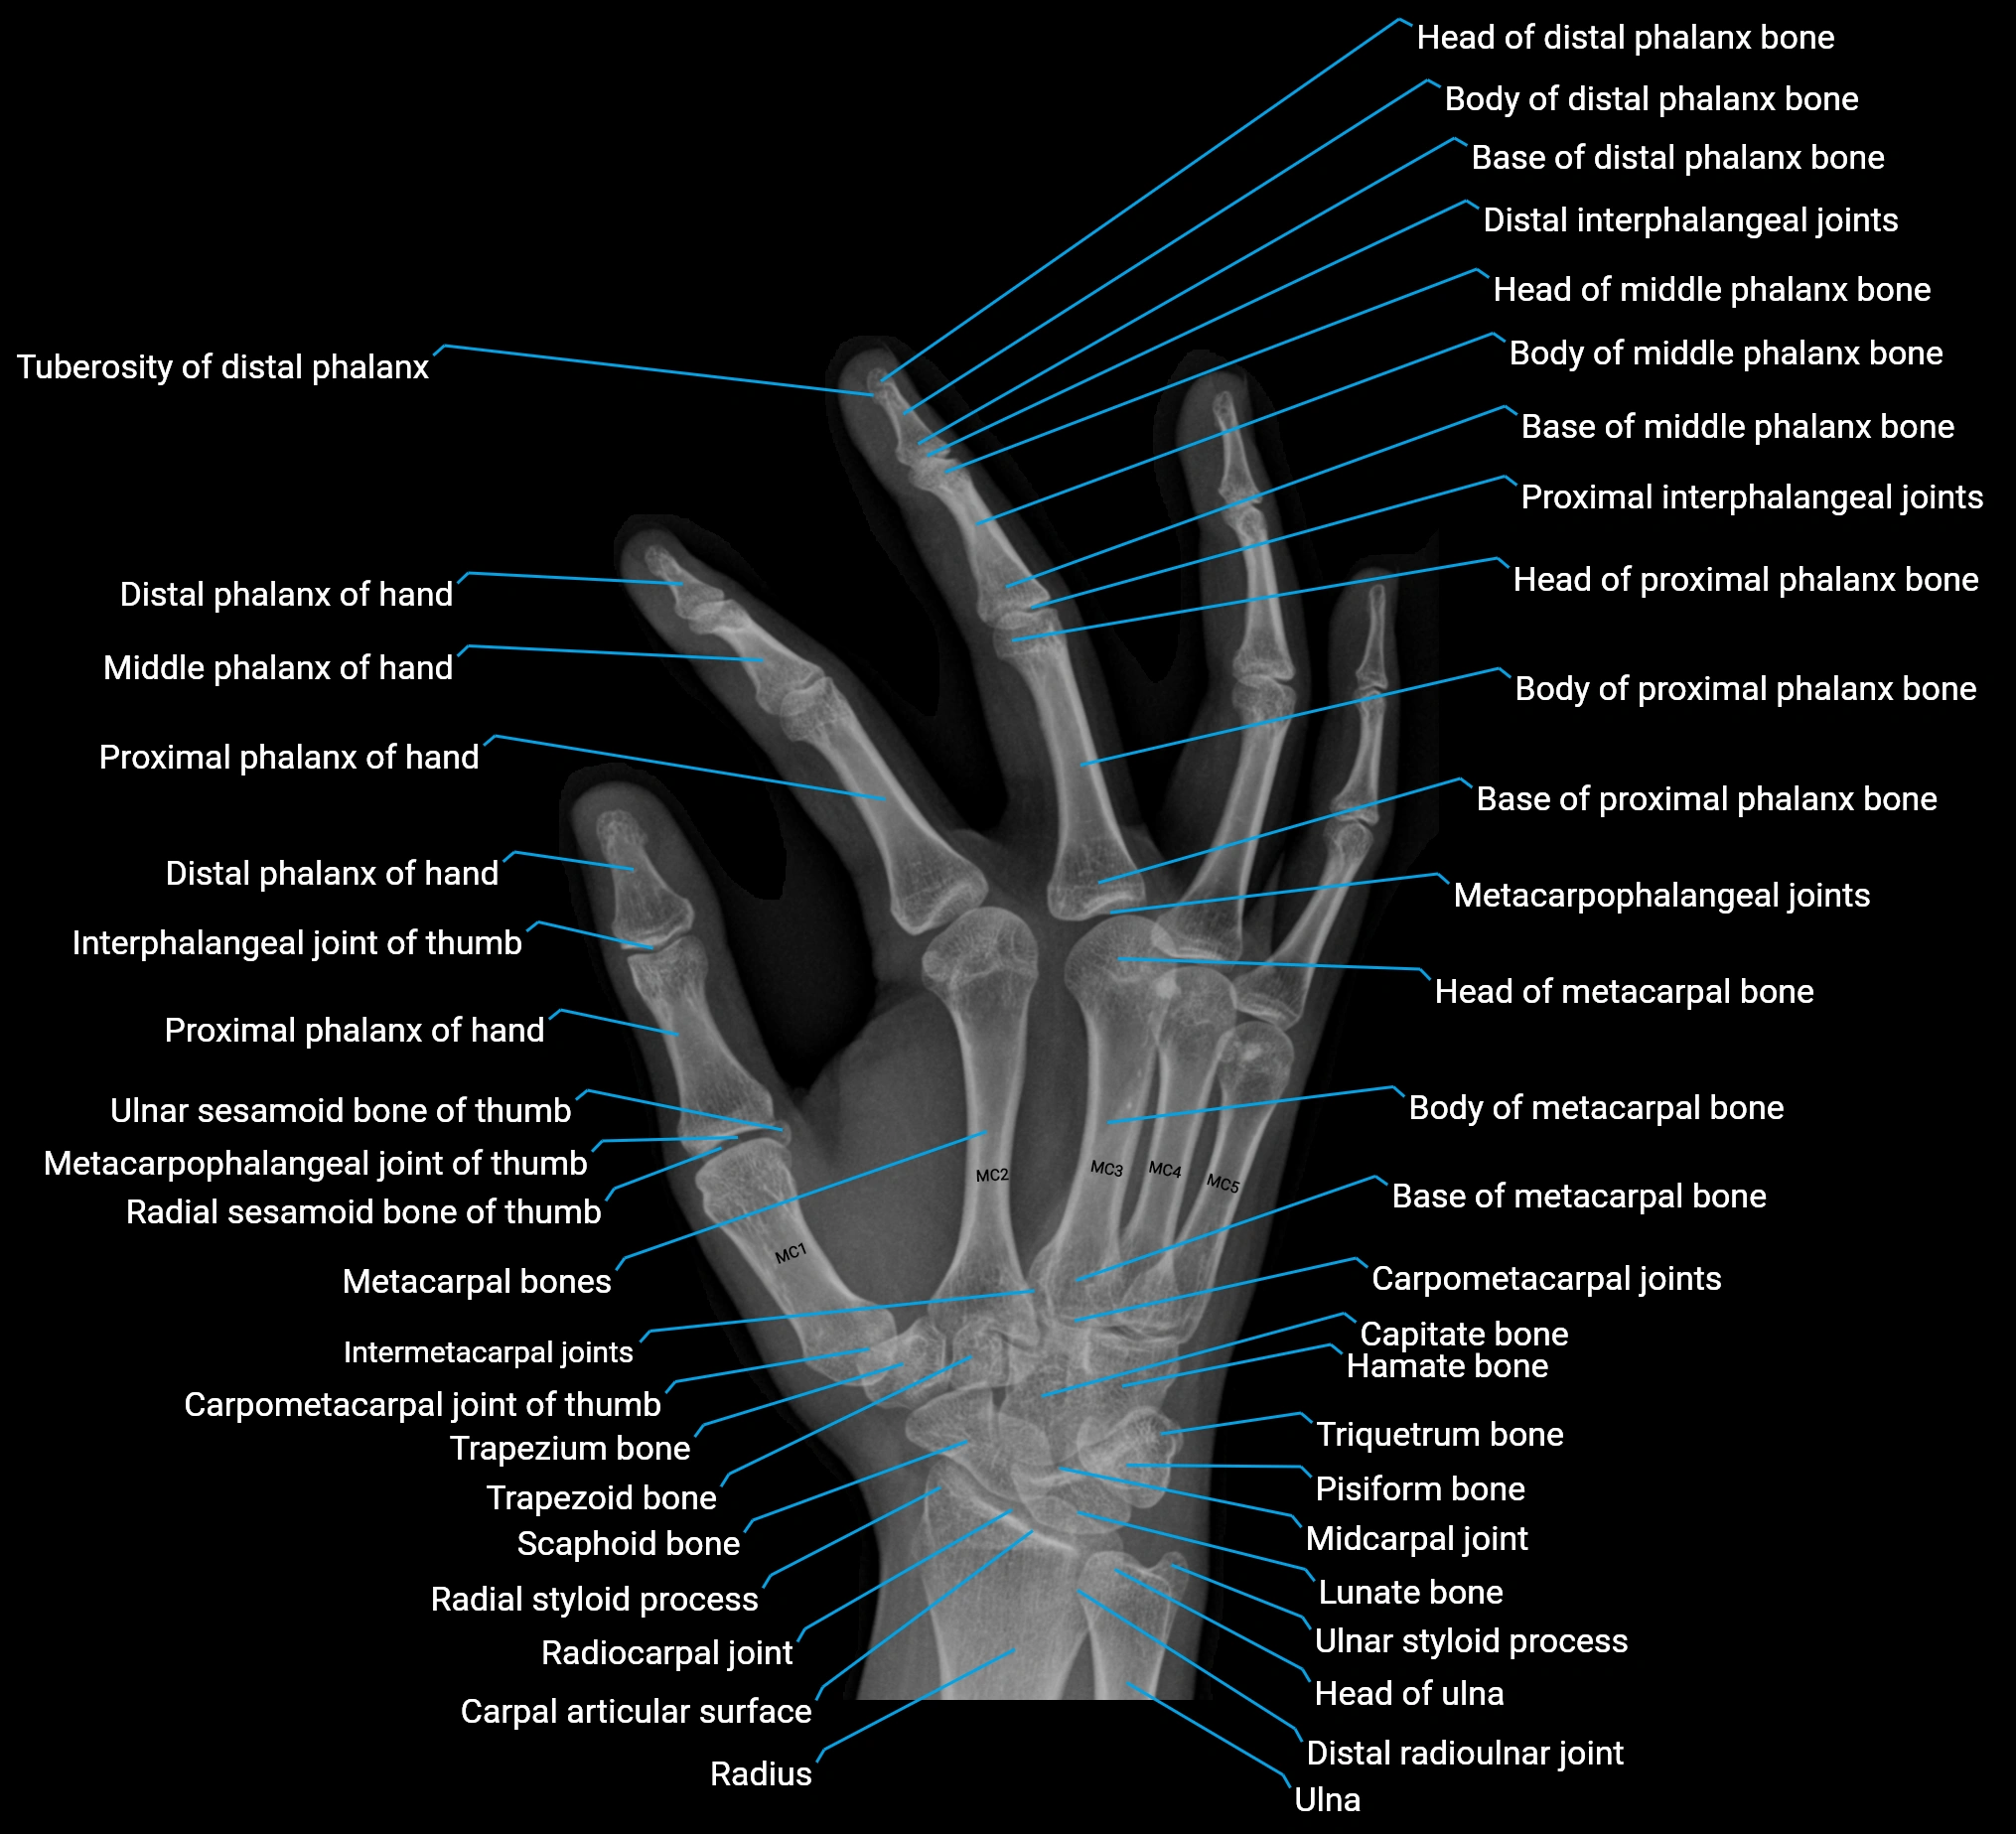

Origin, Course, and Insertion

Origin: From the pisiform bone, the pisohamate ligament, and the tendon of the flexor carpi ulnaris.

Course: Muscle fibers run distally along the ulnar side of the hand, forming a flat tendon near the base of the little finger.

Insertion: Ulnar side of the base of the proximal phalanx of the fifth digit and the extensor expansion of the same finger.

Tendon Attachments

-

The tendon passes along the medial side of the fifth metacarpal and inserts into both the base of the proximal phalanx and dorsal digital expansion.

It may send a slip to the extensor digiti minimi tendon, facilitating combined extension and abduction.

Relations

Superficial: Palmar fascia and skin of the hypothenar eminence

Deep: Flexor digiti minimi brevis and opponens digiti minimi

Medially: Ulnar border of the hand

Laterally: Flexor tendons of the little finger

Proximally: Pisiform and ulnar artery and nerve branches

Distally: Proximal phalanx and extensor expansion of the little finger